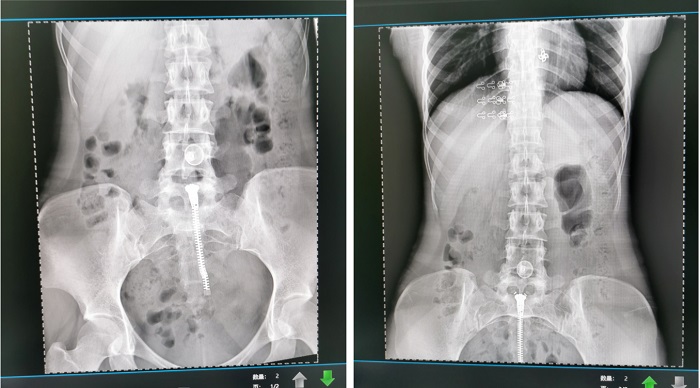

普利德懸吊DR采用高品質平板探測器,滿足人體頭部、胸部、腹部、腰椎、四肢等部位的數字攝影檢查,成像速度快,圖像質量高,可對肺野內細微結構顯示清晰,病變檢出率高,而且降低受檢者所接受的輻射劑量,這些優勢在體檢篩查中對早期發現病變具有重要的意義。